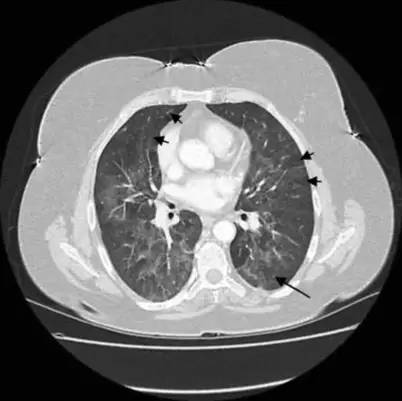

急性期胸部CT表现为两肺弥漫的磨玻璃密度影或广泛的实变影,主要分布在中下肺(如图7)。

图 7:OHP急性期胸部CT表现

2.慢性型主要表现为逐渐加重的呼吸困难,容易疲劳,体重减轻,晚期可出现呼吸衰竭,肺心病体征。

慢性期胸部CT表现为:两肺内不规则的线样、网状、或蜂窝状阴影结节影,靠近胸膜分布局部有磨玻璃样改变,并可见牵张性支气管扩张(图8)。

图 8: OHP慢性期胸部CT表现